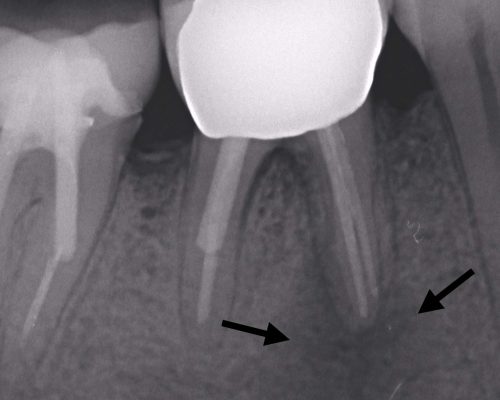

kindtand med rodspidsbetændelse

Rodspidsbetændelse

kindtand lige efter roidspidsoperation

Efter rodspidsoperation

kindtand med heling efter rodspidsoperation

Heling 4 mdr efter operation